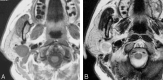

F<sc>ig</sc> 2.

Fig 2.

Case 2. A, Axial T1-weighted image (spin-echo: TR/TE, 650/9.3) shows a lobulated mass in the right parotid gland, with a low-signal-intensity well-defined mass in the right parotid gland. B, Axial T2-weighted image (fast spin-echo: TR/TE, 3150/108) shows a heterogeneous hyperintense mass. C, Axial gadolinium-enhanced T1-weighted image (spin echo; TR/TE, 650/9.3) shows a mass in the right parotid gland with heterogeneous enhancement. D, Coronal STIR image (TR/TE/TI, 3216/36/165) shows a hyperintense mass in the right parotid gland. The tumor is situated directly caudal to the stylomastoid foramen and protrudes into it (arrow).